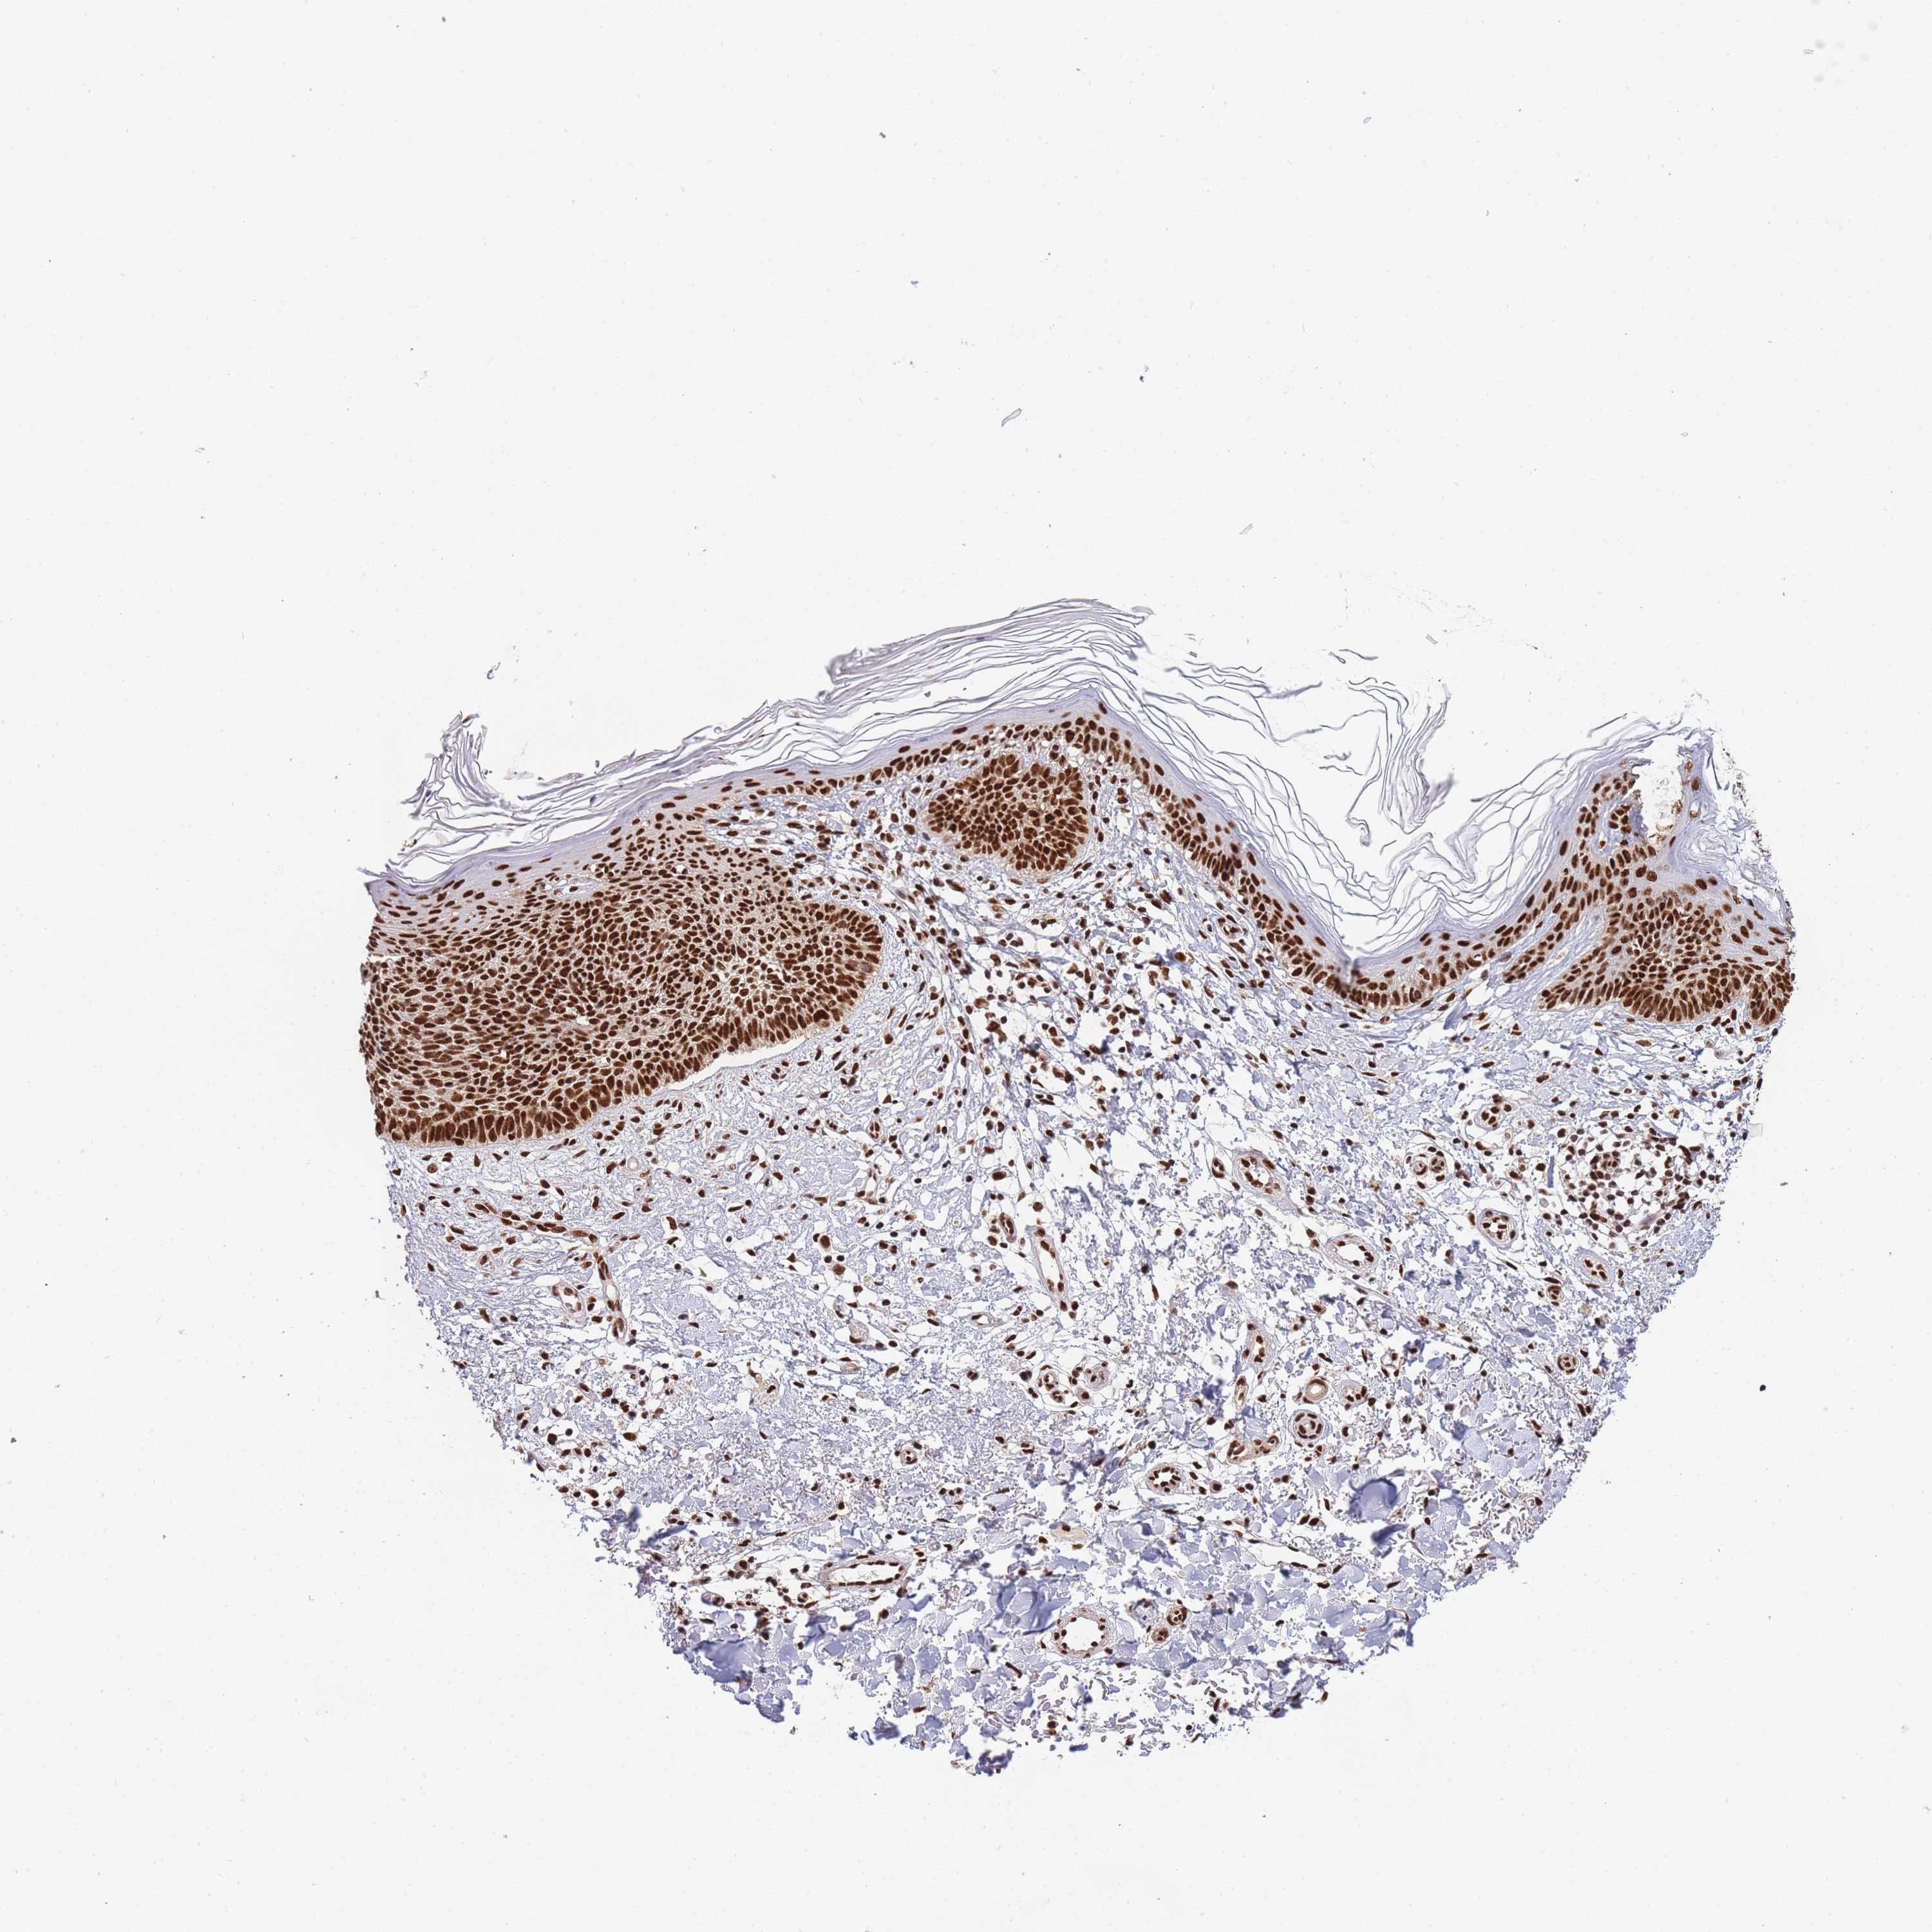

SKIN CANCER - Protein expressioni

A mouse-over function shows sample information and annotation data. Click on an image to view it in a full screen mode. Samples can be filtered based on level of antibody staining by selecting one or several of the following categories: high, medium, low and not detected. The assay and annotation is described here.

Antibody staining in the annotated cell types in the current human tissue is reported as not detected, low, medium, or high, based on conventional immunohistochemistry profiling in selected tissues. This score is based on the combination of the staining intensity and fraction of stained cells.

Each image is clickable and will lead to virtual microscopy that enables deeper exploration of all samples and also displays staining intensity scores, fraction scores and subcellular localization as well as patient and tissue information for each sample.

Antibody CAB005167

Staining

High

Location

Nuclear

Squamous cell carcinoma, metastatic, NOS